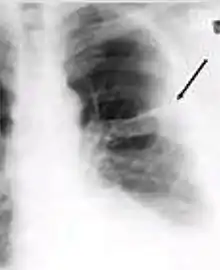

2. Any cavitary lesion - Lucency (darkened area) within the lung parenchyma, with or without irregular margins that might be surrounded by an area of airspace consolidation or infiltrates, or by nodular or fibrotic (reticular) densities, or both. The walls surrounding the lucent area can be thick or thin. Calcification can exist around a cavity.

Chest X-ray of a person with advanced tuberculosis: Infection in both lungs is marked by white arrow-heads, and the formation of a cavity is marked by black arrows.